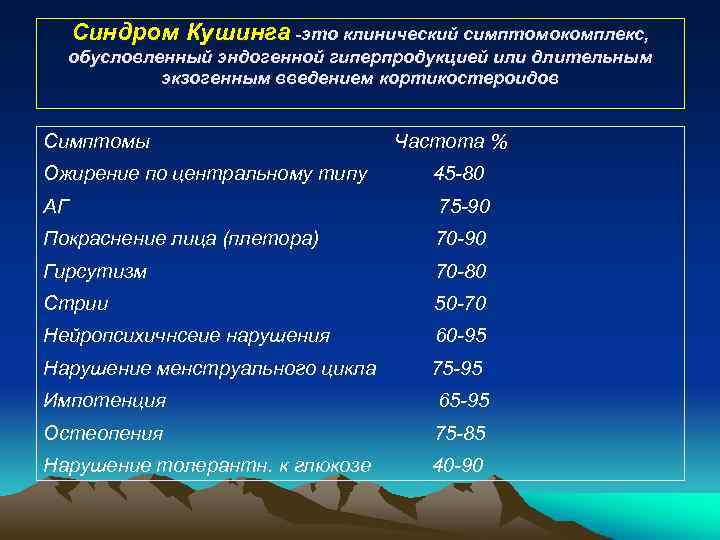

Синдром Кушинга -это клинический симптомокомплекс, обусловленный эндогенной гиперпродукцией или длительным экзогенным введением кортикостероидов Симптомы Частота % Ожирение по центральному типу 45 -80 АГ 75 -90 Покраснение лица (плетора) 70 -90 Гирсутизм 70 -80 Стрии 50 -70 Нейропсихичнсеие нарушения 60 -95 Нарушение менструального цикла 75 -95 Импотенция 65 -95 Остеопения 75 -85 Нарушение толерантн. к глюкозе 40 -90

Синдром Кушинга -это клинический симптомокомплекс, обусловленный эндогенной гиперпродукцией или длительным экзогенным введением кортикостероидов Симптомы Частота % Ожирение по центральному типу 45 -80 АГ 75 -90 Покраснение лица (плетора) 70 -90 Гирсутизм 70 -80 Стрии 50 -70 Нейропсихичнсеие нарушения 60 -95 Нарушение менструального цикла 75 -95 Импотенция 65 -95 Остеопения 75 -85 Нарушение толерантн. к глюкозе 40 -90